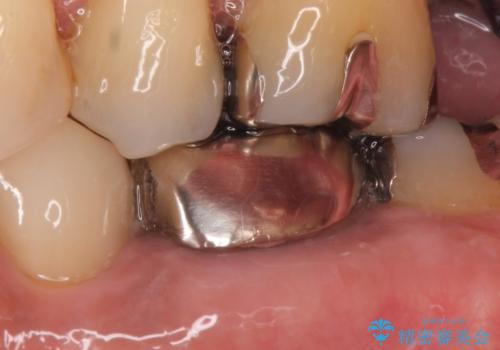

- 左下6番目の銀歯をオールセラミッククラウンにやり替えた症例です。

根管充填が不十分だったため再根管治療も行っております。